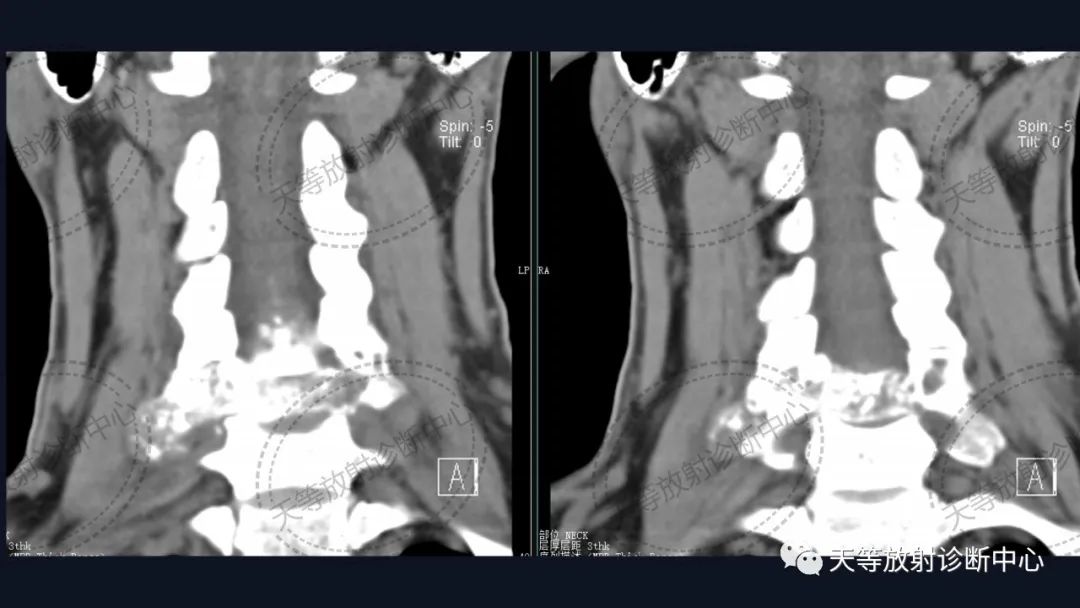

肿瘤复发,椎旁分叶状软组织肿块,内部信号不均,混杂信号,高低信号不等,内见线状小叶间隔。

DWI信号较高,内部钙化灶呈散在泥沙样低信号灶。

诊断软骨肉瘤复发。

病例1:上图:软骨肉瘤。CT显示椎管及其附件骨质溶骨性破坏,椎体周围软组织肿块并含大量钙化影,钙化呈斑片状、斑点状不定型。整个肿块外生性生长为主,局部突入椎管内。